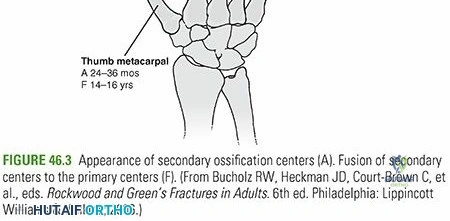

Imaging and Templating

Digital templating is performed to determine the appropriate plate length. A general biomechanical rule for diaphyseal plating is to achieve a minimum of three to four bicortical screws (six to eight cortices) in both the proximal and distal main fracture fragments. A 4.5 millimeter narrow limited contact dynamic compression plate or locking compression plate is typically selected.